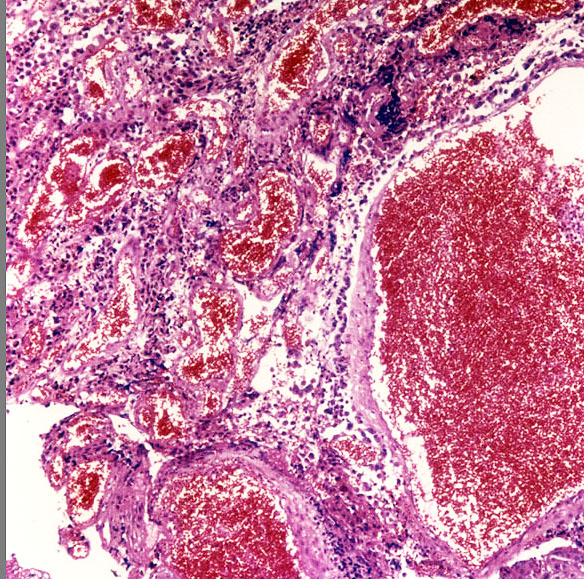

メラノーシスの部分の組織所見です。核の異型性がなくメラニン色素顆粒がみられます。脳底部や小脳の実質内には,散在性にメラニン顆粒を豊富に含む多数の迷入細胞が認められます。くも膜下腔を埋め尽くしたり,軟膜血管に沿って脳の深部に入り込んだり,軟膜から直接脳組織に浸潤したりしています。しかし,脳実質組織構造の乱れはなく,神経機能も侵されないために,局所神経症候を呈することは少ないです。

悪性黒色腫(melanoma) の細胞で,多核の細胞や,細胞の大小不同,核の異型性が目立ち悪性腫瘍の所見です。右の画像では大小の血管が腫瘍組織の間に発達しています。非常に血管に富む腫瘍です。